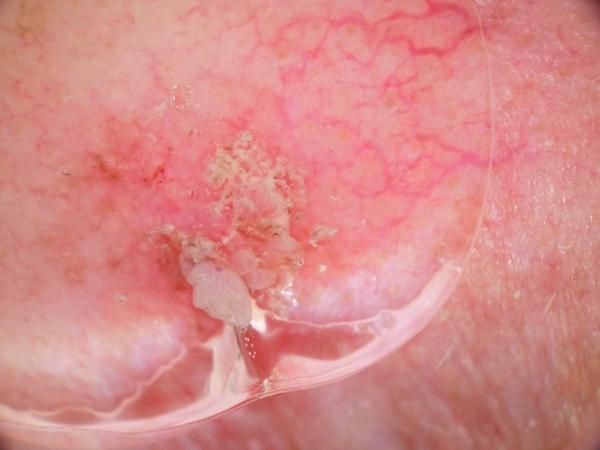

MILK10k consists of 10480 images, each representing a paired clinical close-up and dermatoscopic image for 5240 lesions. The dataset’s metadata include age (in 5-year intervals), sex, anatomic site, skin tone, diagnosis, method of ground truth establishment (histopathology or other means), and, if a dermatoscopic image of the same lesion was previously included in ISIC, its corresponding ISIC identifier. Skin tone is categorized into six levels, ranging from very dark (0) to very light (5), intentionally distinct from the Fitzpatrick skin types to avoid confusion. Most patients had skin tones in the middle ranges. Of the 5240 lesions, 95.7% were biopsied or excised, with histopathology serving as the gold standard for diagnosis. Diagnoses were mapped to both the ISIC-Dx diagnostic scheme and a simplified classification based on the ISIC2018/2019 challenge and HAM10000 diagnostic categories. The dataset includes 11 broad diagnostic categories: